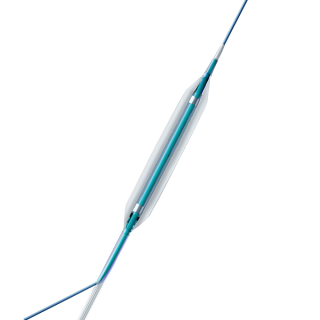

EverFlow® is a Paclitaxel-coated Rapid Exchange PTCA Balloon Catheter with a drug releasing balloon system for the treatment of coronary vessels. EverFlow® is designed to improve the lumen diameter and to reduce restenosis in the treatment of lesions in native coronary arteries.